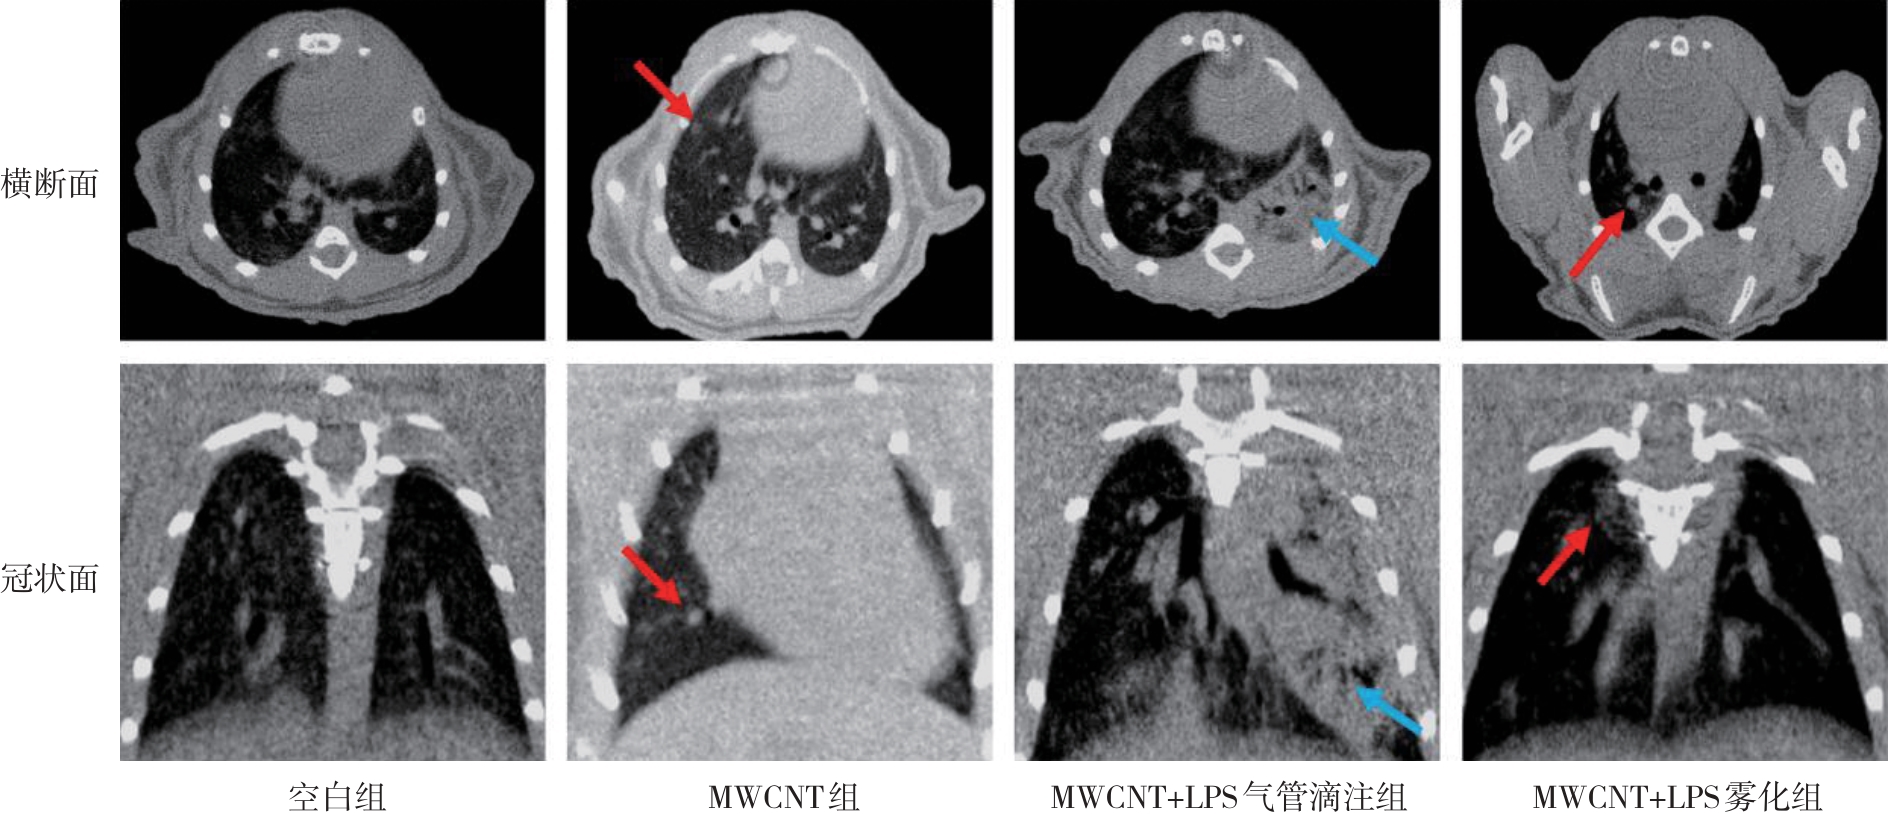

• 不同模型复制方式致肺结节小鼠模型的比较研究

2025, 35(19):21-30. DOI: 10.3969/j.issn.1005-8982.2025.19.004

摘要 (213) HTML (83) PDF 4.23 M (69) 评论 (0) 收藏

摘要:目的 比较多壁碳纳米管(MWCNT)、MWCNT+脂多糖(LPS)气管滴注、MWCNT+LPS雾化3种方法复制的肺结节小鼠模型,为后续研究提供依据。方法 将40只雄性C57BL/6小鼠随机分为空白组、MWCNT组、MWCNT+LPS气管滴注组与MWCNT+LPS雾化组,每组10只。空白组小鼠气管滴注同体积生理盐水,其余各组均气管滴注60 μL 8 mg/kg MWCNT悬液,在此基础上,MWCNT+LPS气管滴注组联合进行气管滴注LPS溶液(5 mg/kg, 7 d/次),MWCNT+LPS雾化组联合进行雾化吸入LPS溶液(5 mg/mL,30 min/次,7 d/次),共28 d,第29天取材。检测小鼠肺功能[潮气量(TV)、每分钟通气量(MV)、特殊气道阻力(sRaw)、功能残气量(FRC)],观察小鼠肺部影像学及组织病理学,免疫组织化学法检测巨噬细胞标志物F4/80和淋巴细胞标志物CD3+T蛋白表达,检测支气管肺泡灌洗液(BALF)中炎症细胞分类计数,LDH和BCA法检测肺损伤,血细胞分类法检测白细胞比例,酶联免疫吸附试验检测肺泡灌洗液(BALF)中干扰素-γ(IFN-γ)、肿瘤坏死因子-α(TNF-α)与白细胞介素-2(IL-2)水平。结果 各组小鼠的TV、MV及FRC水平比较,差异均无统计学意义(P >0.05);各组小鼠sRaw水平比较,差异有统计学意义(P <0.05),MWCNT+LPS气管滴注组小鼠sRaw水平增加。肺部影像学显示,MWCNT组小鼠右肺可见一类圆形实性结节,MWCNT+LPS气管滴注组小鼠左肺可见片状磨玻璃样改变,MWCNT+LPS雾化组右肺可见一单发小斑片状改变。肺部组织病理学显示,空白组小鼠肺部光滑质嫩;MWCNT组小鼠肺部有黑色沉积影,表面有白色小结节;MWCNT+LPS气管滴注组肉眼可见大量黑色碳纳米粒沉积物,伴有大量白色结节形成;MWCNT+LPS雾化组小鼠肺部质嫩,中央部有大量黑色沉积物,可见团状小结节。HE染色显示,空白组小鼠肺泡管和肺泡规整,MWCNT组小鼠肺脏可见多灶性轻微肉芽肿,MWCNT+LPS气管滴注组小鼠肺脏可见中度多灶性肉芽肿,MWCNT+LPS雾化组小鼠肺脏可见多灶性轻微肉芽肿。免疫组织化学染色结果显示,与空白组相比,MWCNT组小鼠F4/80和CD3+T均在肺组织中少量浸润;MWCNT+LPS气管滴注组的F4/80呈灶状浸润,胞质染色强阳性,CD3+T细胞呈局灶性分布;MWCNT+LPS雾化组的F4/80与CD3+呈弥散性浸润,在组织间质中广泛分布。与空白组相比,MWCNT组、MWCNT+LPS气管滴注组、MWCNT+LPS雾化组小鼠BALF中性粒细胞数均增加(P <0.05),MWCNT+LPS气管滴注组出现大量巨噬细胞。各组小鼠BALF的LDH值比较,差异有统计学意义(P <0.05);与空白组相比,MWCNT组LDH值差异无统计学意义(P >0.05),MWCNT+LPS气管滴注组LDH值升高(P <0.05)。各组小鼠BALF的BCA比较,差异无统计学意义(P >0.05)。与空白组相比,MWCNT+LPS气管滴注组的单核细胞和嗜酸性粒细胞计数升高(P <0.05);MWCNT+LPS雾化组小鼠嗜酸性粒细胞计数升高(P <0.05),中性粒细胞、淋巴细胞及单核细胞比较,差异无统计学意义(P >0.05)。与空白组相比,MWCNT组TNF-α水平升高(P <0.05),INF-γ、IL-2水平比较,差异无统计学意义(P >0.05);MWCNT+LPS气管滴注组的INF-γ、TNF-α、IL-2水平均升高(P <0.05);MWCNT+LPS雾化组的INF-γ、TNF-α、IL-2水平也均升高(P <0.05)。结论 MWCNT、MWCNT+LPS滴注和MWCNT+LPS雾化3种方法均可成功复制肺结节模型,其中MWCNT+LPS雾化方法复制的肺结节模型能够有效模拟人类结节病理生理学的多个关键特征,是肺结节机制研究和药物开发的有价值实验模型。

• 0+1

• 1+1

• 2+1

• 3+1

• 4+1